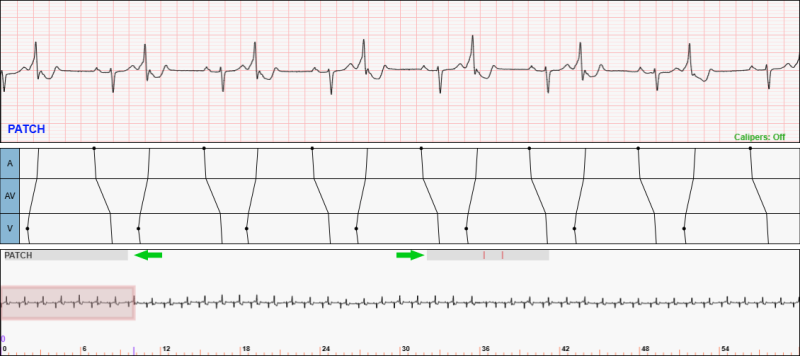

Fig. 10: An example showing the information regions in the Navigator Window. In this ECG, the lead is “PATCH”, two regions contain ladder diagrams (the two grey regions highlighted by green arrows), and two annotations have been added to the Analysis Window.

Fig. 11: The same ECG from Figure 10 with the Naviator Box moved to overlap the left grey region. Notice the annotations in the Analysis Region. Notice the time of the left edge of the Navigator Box is shown in the bottom region. In this case, the time is 9.91 seconds into the ECG.

The Navigator Region contains two information regions:

1. The Top Region: located at the top of the Navigator Window

• The active lead is shown in the upper left corner

• If present and ladder diagrams have been toggled on, the grey-shaded regions indicate where ladder diagrams have been drawn for the ECG

• If present and annotations have been toggled on, colored vertical lines indicate where annotations have been added to the Analysis Window for the ECG

2. The Bottom Region: located at the bottom of the Navigator Window

• Show the time into the ECG

Examples of these regions are shown in Figures 10 and 11.